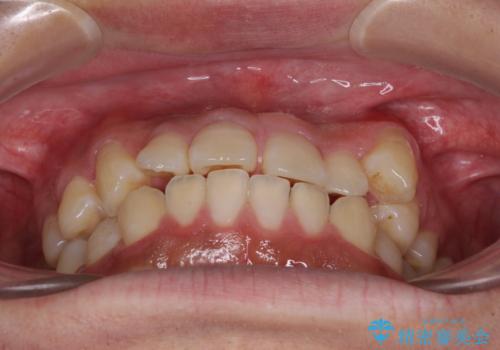

- 八重歯と前歯の隙間を気にして来院された患者様です。

八重歯の改善のため、奥歯を後方に移動させていくこととし、患者様と相談の上、ワイヤー装置にて矯正治療を行うこととしました。

上顎前歯正中の隙間は、舌突出癖によるものと考えられ、舌のトレーニングによる悪習癖改善が必須であるため、徹底するよう指導してから治療を開始することとしました。

舌突出癖が改善されず、なかなか正中の隙間や上下の前歯が接触しなかったために治療が長期化してしまいました。

また、治療期間中のプラークコントロールが悪く、ブラッシング指導も奏功しなかったため、装置の周りが脱灰した状態(初期むし歯)となってしまいました。